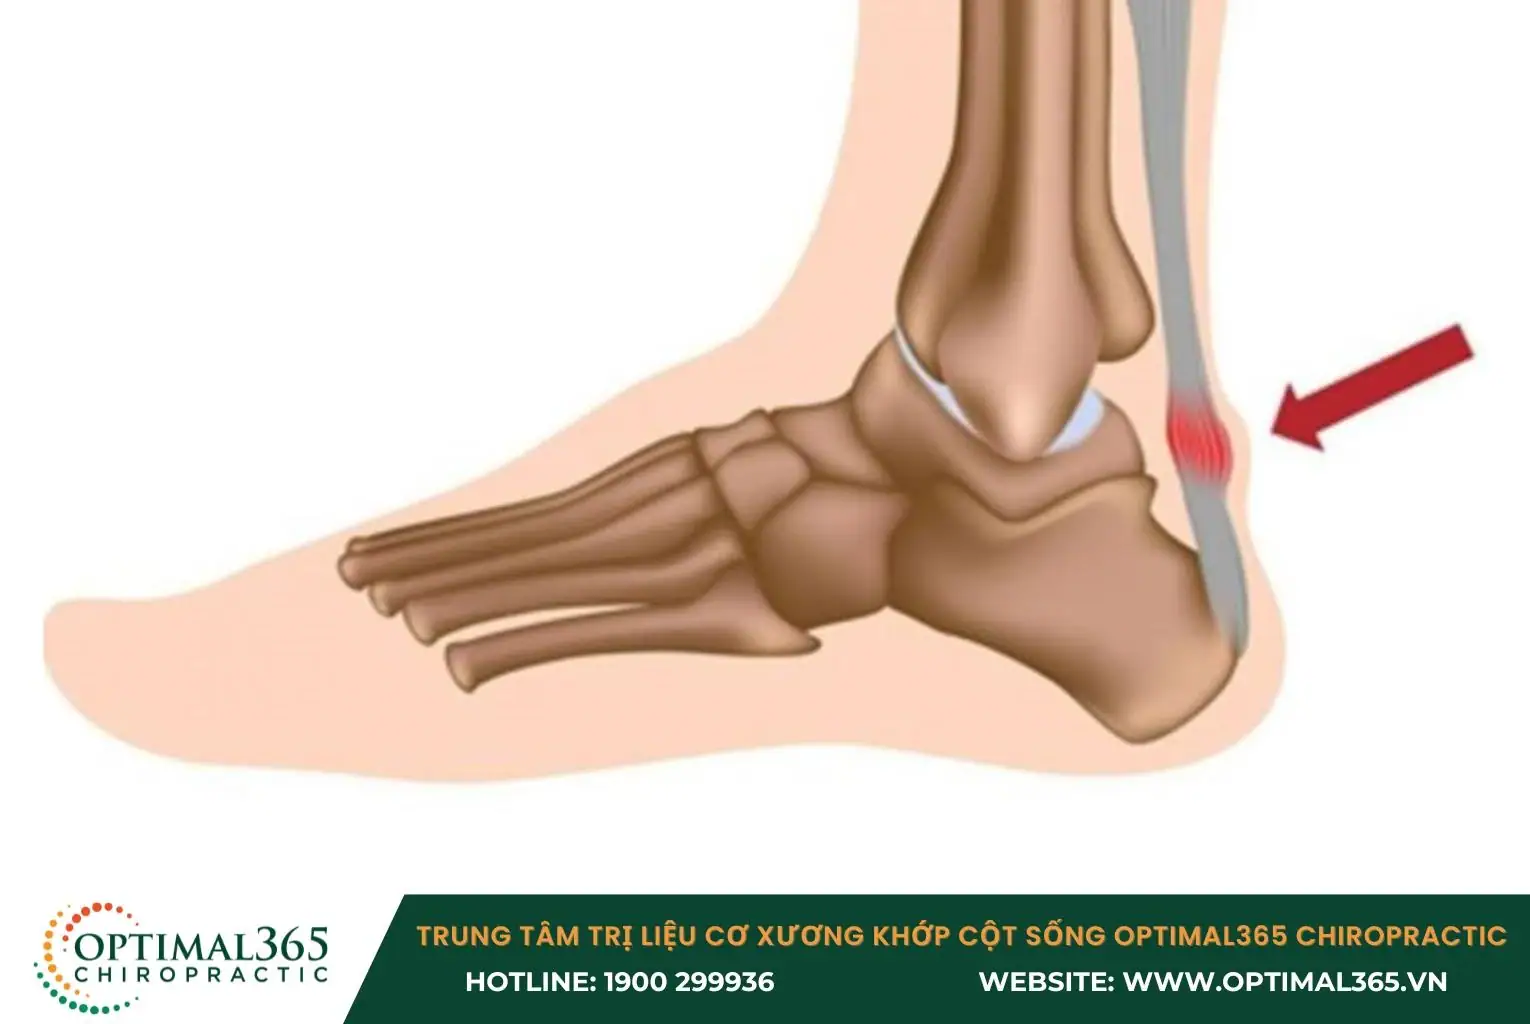

- Viêm gân Achilles (Achilles Tendonitis): Gân Achilles là gân lớn nhất trong cơ thể, kết nối cơ bắp chân với xương gót. Do đó, bất kỳ tổn thương nào ở gân này đều có thể tác động đến bắp chân. Ngoài viêm và đau nhức, các triệu chứng khác bao gồm tê bì, cứng ở bắp chân vào buổi sáng, Việc cử động bàn chân trở nên khó khăn hơn.